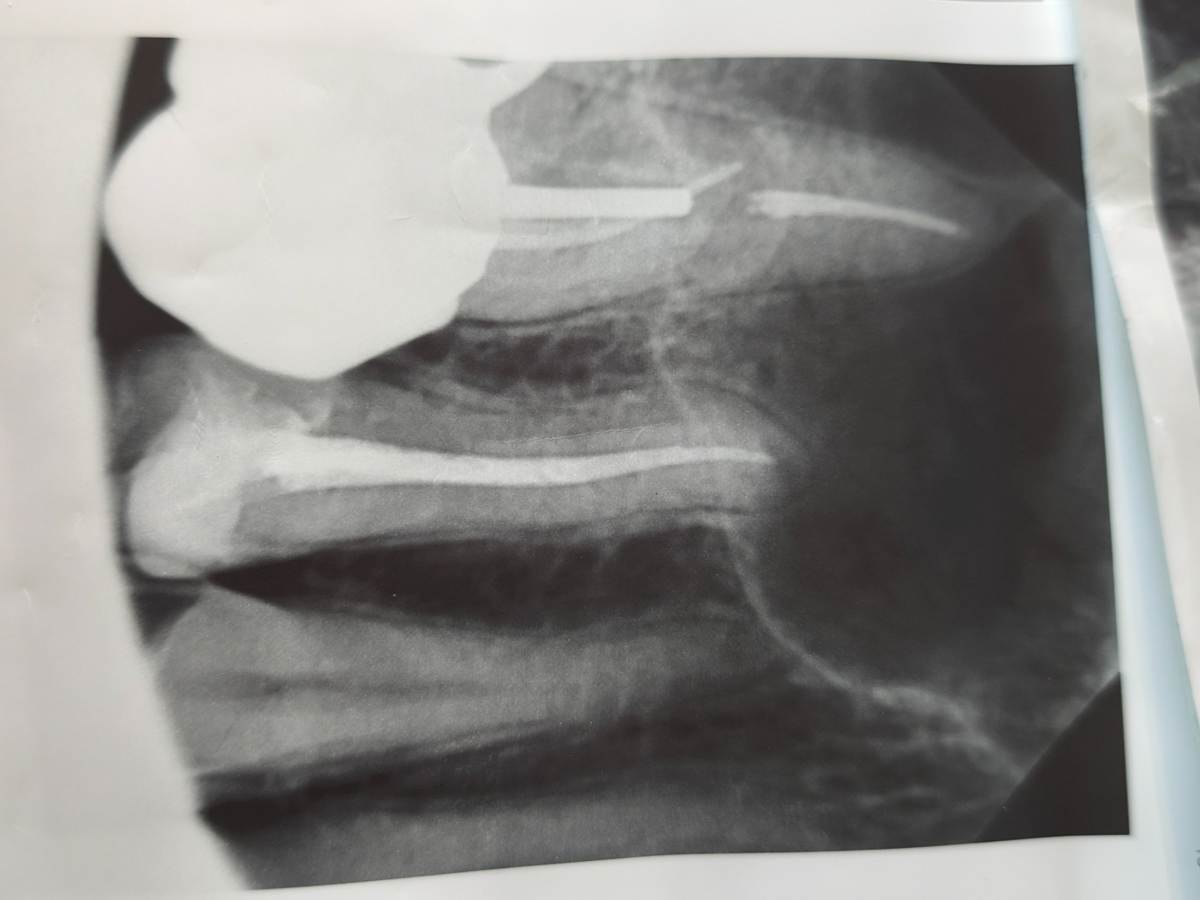

qwerty26 Опубликовано 3 часа назад Поделиться Опубликовано 3 часа назад (изменено) Добрый день. На снимке верхняя 6 с коронкой, до установки лечила год кисту. Перед лечением кисты рядом была пролечена 5 ( другим стоматологом и как оказалось слегка недопломбирован канал), но она всё время поднывает, с доктором решили, что возможно из-за кисты. Полгода хожу уже с коронкой, но 5 так и поднывает, ну или десна под ней. По ней слегка ощутимо стучать и надавливать, 6 зуб не беспокоит. Нужно ли тут что-то перелечивать и не киста ли это на снимке? Заранее спасибо. Изменено 3 часа назад пользователем qwerty26 Ссылка на комментарий

red_butler Опубликовано 1 час назад Поделиться Опубликовано 1 час назад Здравствуйте, по снимку с пятым зубом все нормально. Сделайте кт Ссылка на комментарий